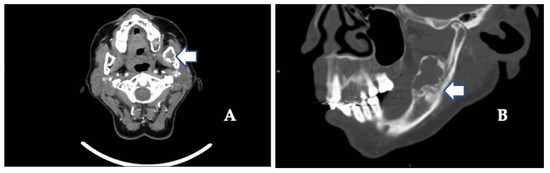

The usual diagnostic imaging study with a panoramic radiograph showed a well-defined mixed radiolucent–radiopaque lesion with peripheral enhancement in the left mandibular ramus occupying almost its entire thickness (Figure 1). Computed tomography performed with contrast was used to confirm the existence of a heterogeneously enhancing 3 cm long tumor with lobulated margins and bicortical expansion without bone perforation. Radiographically, there appeared to be an expansile cystic mass with areas of calcification and sclerotic borders. The mandibular lower border was intact (Figure 2A,B).

Figure 2. (A) Contrast-enhanced computed tomography scan showing the extent of the tumor along the mandibular angle (see arrow) (coronal image). (B) Sagittal view shows mixed radiolucent–radiopaque lesions (see arrows) and advanced osteoarthritic changes in the left temporomandibular joint (see arrow).